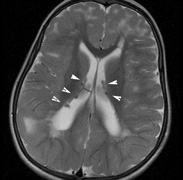

- Cognitive impairment. Thirty percent to 60% of children with NF1 have learning difficulties, which

are typically mild and nonprogressive. These include visual-spatial

problem-solving difficulty, language disorders, and attention

deficit disorder. The reason for this is not clear but may be related

to unidentified bright objects (UBOs) seen on T2-weighted

brain magnetic resonance imaging (MRI) scans. These hyperintensities

are common in young patients with NF1 but decrease with advancing

age. The histopathologic correlate of UBOs is unclear. It has

been postulated that the prevalence of learning difficulties in children

with NF1 may be related to heterozygosity of the NF1 gene (i.e., the gene may have additional functions that affect cognition when the

full complement of its gene product is not expressed in the central nervous

system).25,32–34